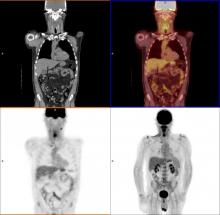

This is a walk around of an innovative new SPECT-CT nuclear imaging system shown at the Radiological Society Of North America (RSNA) 2018 meeting this week. It's CT system with comes in 16, 64 or 128 slice configurations. It has 12 SPECT detector robotic arms that automatically move toward the patient and use a sensor to stop a few millimeters from the skin to optimize photon counts and SPECT image quality. It also uses more sensitive CZT digital detectors, which allows either faster scan times, or use of only half the radiotracer dose of analog detector scans.